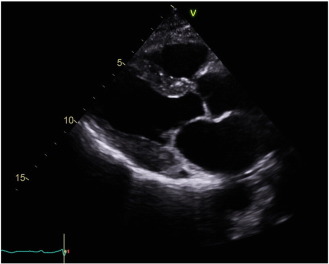

Fig. B.3.

“Bulls-eye” strain pattern of cardiac amyloidosis.

Echocardiography suggested statistically significant regression in the cardiac amyloid process, similar to what had previously been reported [18]. Wall thickness significantly reduced, atrial size shrunk, and measures of diastolic function improved (see Fig. B.1 ;  Fig. B.2). The ejection fraction did not significantly change. Myocardial strain analysis at late follow-up suggested better global longitudinal strain in this highly selected group of survivors, than many cardiac amyloid studies have suggested (the global longitudinal strain was more negative than previously reported for cardiac amyloid patients) [13]; [25] ;  [26]. The mean global longitudinal strain was − 16%. The classical bulls-eye pattern of cardiac amyloidosis was only seen in 50% of these patients [13] ;  [26] (see Fig. B.3 and Table A.2). Strain had not been assessed before PBSCT for any of the patients in this study.

Repeat echocardiography on the day of the CMR at late follow-up confirmed that patients still had macroscopic regression of cardiac infiltration, based on the echocardiographic images. There was marked improvement in echocardiographic anatomical and functional parameters compared to the pre-PBSCT echocardiograms. The post-PBSCT echocardiograms showed near normal global longitudinal strain. The classical bulls-eye pattern of cardiac amyloidosis [13] was seen in 50% of these echocardiograms. The CMR scans in this study showed similar wall thicknesses to that shown on echocardiography, supporting the suggestion that disease regression can occur in cardiac amyloidosis.